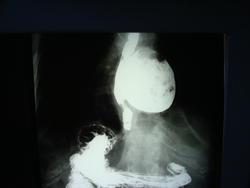

С контрастированием будут снимки чуть позже. Я в принципе, думал до контрастирования,  так же как коллеги, но оказалось не то. Есть жалобы на дисфагию.Может у кого-то будут другие версии?

Жалутся на выраженные приступообразные в области нижней части грудины, дисфагию.

Дивертикул н/3 пищевода с явлениями дивертикулита( краевой дефект наполнения-озлокачествление?...)

1. Алмо - спасибо за наблюдение, уж такого дивенртикула не видал - гигант.

3. Юлии - это не озлокачествление, это - кусочек пищи, так думаю.

Да, это куски пищи. Не создалось впечатление об опухолевом поражении. Думаю, надо расценивать как явления дивертикулита.

Красивый случай. По всей видимости "ценкеровский дивертикул" или по типу "ценкеровского"?

Не совсем, ценкнеровский- это пищеводно-глоточный дивертикул, который правда так же, может быть больших размеров.

"Киллиан – Джеймисон - дивертикул", который локализуется именно там...